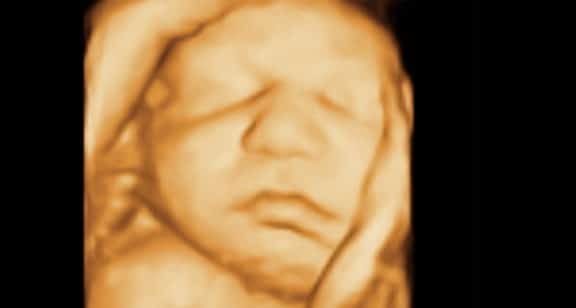

O Bebê A maior parte do vérnix (ou lanugo) já desapareceu e o bebê se prepara para nascer em poucos…